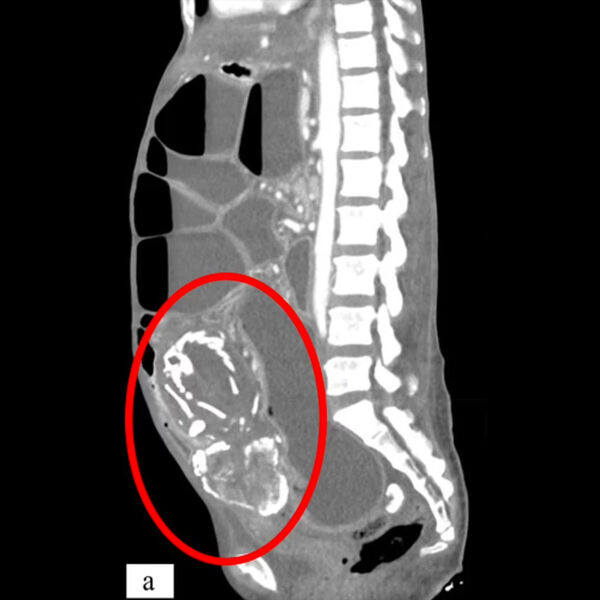

Врачи из Медицинского университета SUNY Upstate рассказали о случае смерти женщины из Конго из-за тяжелого голода, вызванного сдавлением тонкой кишки окаменевшим плодом ребенка, который она носила в своем теле около девяти лет. О случае сообщает Daily Mail.

Женщина родом из Конго обратилась к врачам в Нью-Йорке с жалобами на спазмы желудка. Сканирование обнаружило в теле 50-летней женщины литопедиона —«каменного ребенка», представляющего собой кальцифицированный плод.

Это редкое явление было зарегистрировано менее 300 раз, впервые — во Франции в 1582 году. Плод может кальцифицироваться, умерев при внематочной беременности. В некоторых случаях женщины вынашивают плод десятилетиями, не зная об этом.